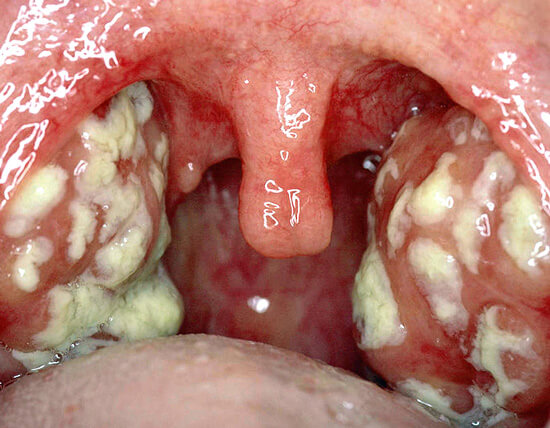

Возьмите ложечку чайную и фонарик и посмотрите горло, если на миндалинах есть налёт то ангина

. Я постоянно проверяю при простуде миндалины , если налёт, сразу вызываю неотложку, чтоб пришёл врач выписыл антибиотик, чем раньше его принимать тем лучше.

Спасибо! Очень наглядно. У нас не так страшно, тьфу три раза. Но картина ясна - ангина без сомнения(( Начинаем антибиотик.

Общий анализ крови. Также выше писали про тест на ангину в аптеке. И картинка с ангинным горлом тоже очень наглядна. При ангине воспаляются миндалины, они так сильно увеличиваются, что могут полностью горло перекрыть, но это в более запущенных случаях, наверно. И налёт на гландах такой бело-серый, блямбами) при ОРВИ краснеет обычно дужка горла. А у нас были волдырики на горле, но тоже на дужках, поэтому я и подумала, что это не ангина.